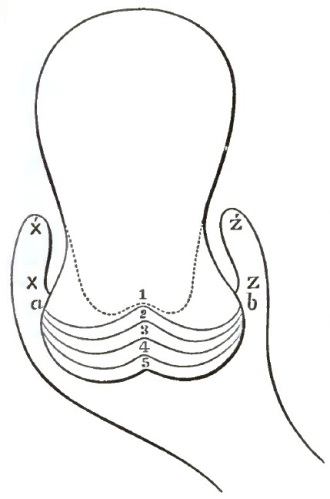

| 1. | THE CLASSICAL REPRESENTATION OF THE PELVIC ORGANS |

| 2. | THE CORRECT REPRESENTATION OF THE PELVIC ORGANS |

| 25. | DIAGRAM SHOWING MUSCULAR STRATA OF UTERUS, AS DIVIDED FOR CLINICAL PURPOSES |